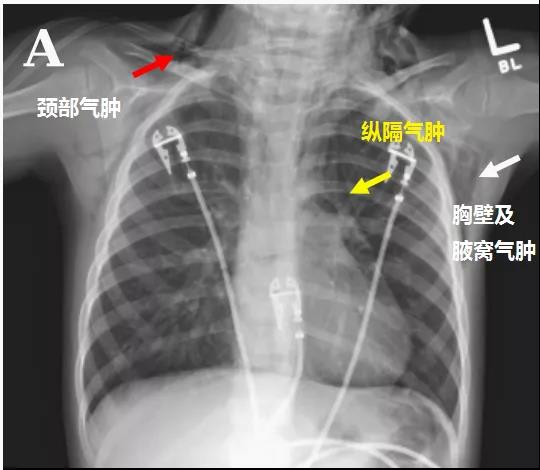

頭顱、胸部CT提示廣泛皮下氣腫、縱隔氣腫、心包積氣、甚至眼眶周圍都積氣,眼球突出!頸部無感染征象,腸管無破裂征象,看來氣體還是來自肺部。但是,肺部無感染、無肺大泡、無劇烈咳嗽,只有間質性肺氣腫。縱隔氣腫、皮下氣腫的治療,核心是根除病因,切開引流效果不像氣胸那么理想,而且縱隔切開引流還存在手術風險。找不到病因,如何是好?考慮患者是過敏體質,有皮疹,繼續呼吸機輔助呼吸,先治療過敏,肌肉注射腎上腺素、靜脈注射類固醇激素和抗組胺藥、吸入支氣管擴張劑等。經上述治療,臨床表現和影像學方面都有迅速的改善。隨后拔出氣管導管,口服類固醇激素出院,門診隨訪。

皮下氣腫、縱隔氣腫突然莫名其妙的就消失了!呼吸機治療可是會加重縱隔氣腫啊!這個皮下氣腫、縱隔氣腫,真的是來去一陣風啊,堪稱神出鬼沒!過敏反應一般表現為皮疹、皮膚瘙癢,嚴重的表現為休克,甚至引起喉頭水腫、氣管和支氣管痙攣及肺水腫導致呼吸困難,其他表現有昏迷、剝脫性皮炎型藥疹等多器官損害。沒聽說過敏反應還會導致廣泛皮下氣腫、縱隔氣腫、心包積氣,甚至眼眶周圍都積氣,眼球突出啊!過敏反應可引起急性支氣管痙攣,進而氣道壓力升高,導致肺泡破裂,空氣進入組織間隙,并沿肺間質內血管鞘進入縱隔,導致縱隔氣腫,只形成間質性肺氣腫,并不會導致我們平時所見的氣胸。這個病例提供了一個罕見的藥物過敏反應方面的臨床表現,對于存在這種特異質的兒童來說,如果不早發現、早治療,隨時可能致命。另外,大家有沒有發現,患者因咽炎口服阿莫西林,才吃了1次,后來過敏,咽炎沒繼續治療,也好了!在患者的咽炎治療過程中,阿莫西林除了引起危及生命的過敏反應,并未扮演其他有任何價值的角色!Jacob A. Kaslow, MD,Elizabeth J. Snyder, MD,Brian C, et al. Massive Facial, Neck, and Chest Air Leaks Following Amoxicillin-Related Anaphylaxis in a Young Child. AJRCCM Articles in Press. Published on 10-January-2020 as 10.1164/rccm.201908-1596IM.